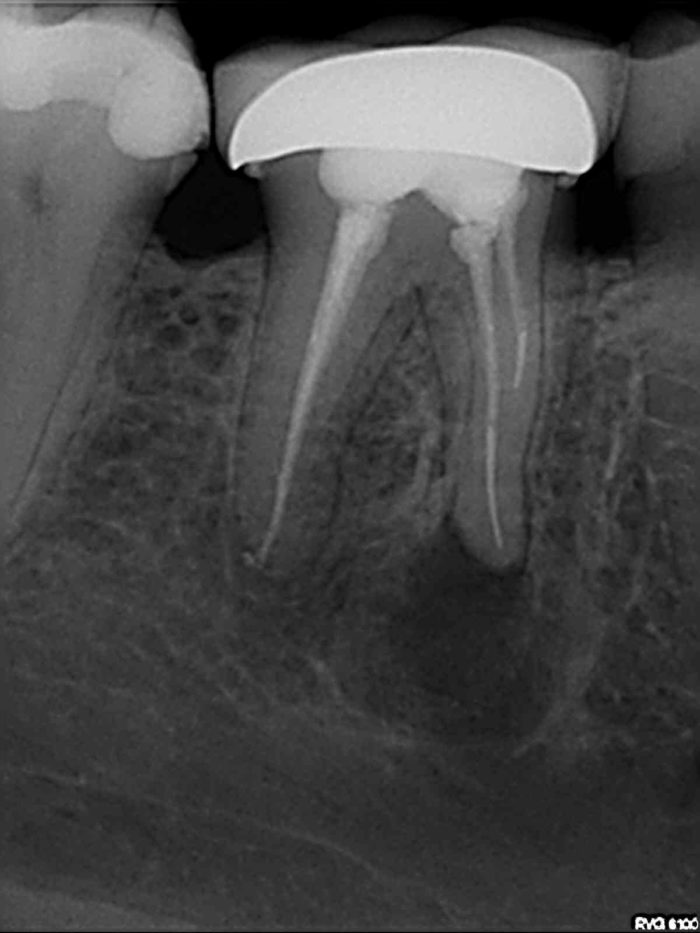

The endo expert managing curved canals Dentistry Online

From dentistry.co.uk

The endo expert managing curved canals Dentistry Online Endo Surgery Meaning Surgery may also be needed to remove calcium deposits in root canals, or to treat damaged root surfaces or the. It aims to preserve the uterus and the ovaries. Endodontists are experts in endodontic surgery. However, surgery can help to relieve pain, and laparoscopic surgery can potentially help you get pregnant. If you have endometriosis and. Surgery is necessary to. Endo Surgery Meaning.